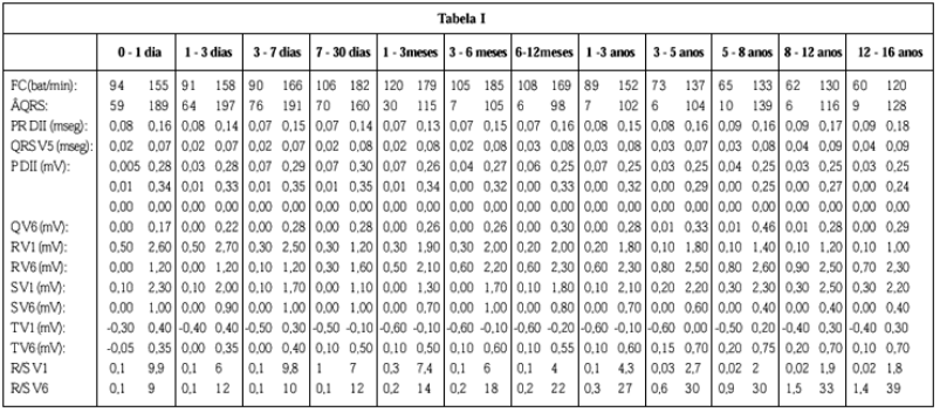

Já quando o assunto é ECG pediátrico, a coisa fica diferente. É preciso normatizar a análise de acordo com uma tabela conhecida como Tabela de Davignon (Figura 1). Nela, você encontra uma série de valores de referência para diversos aspectos do ECG como FC, duração do QRS ou do intervalo PR, entre outros, de acordo com a idade. A gente vai falar sobre isso especificamente num artigo de ECG pediátrico.

O interessante nesse momento é saber que, dependendo da fase da vida da criança – e isso pode incluir a diferença de meses ou mesmo dias! -, o valor da FC pode variar e chegar até 185 bpm e ainda ser considerado normal para aquela faixa etária. Portanto, fique ligado na idade do paciente e não saia por aí dizendo que todo ECG com mais de 150 bpm é, sem dúvida, uma taquicardia.

E pra terminar, é importante lembrar que o ECG é considerado pediátrico para pacientes até 16 anos e, justamente a última faixa de referência, 12 a 16 anos, é legal que você saiba de cor quando for fazer a análise: a FC é normal entre 60 e 120 bpm.

Figura 1: Tabela de Davignon, ferramenta na análise de ECGs pediátricos.